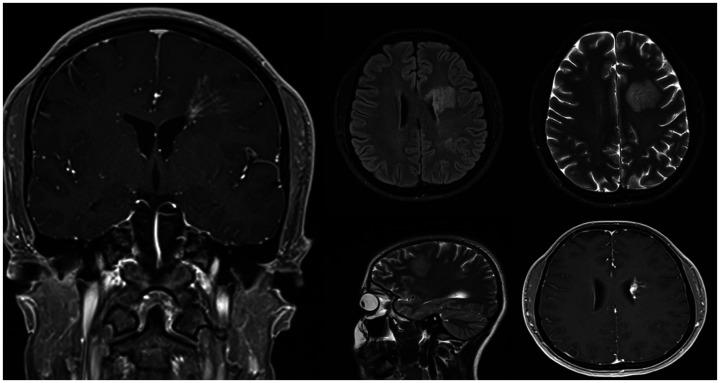

Case: We present a unique case of SLIPPERS observed in a 26-year-old woman with no notable medical or familial background. Laboratory findings ruled out certain diseases from the list of differentials and cranial MRI showed T2 hyperintense areas with linear-patchy enhancements, a pattern consistent with SLIPPERS syndrome. Consequently, patient was diagnosed with SLIPPERS syndrome and received methylprednisolone therapy.